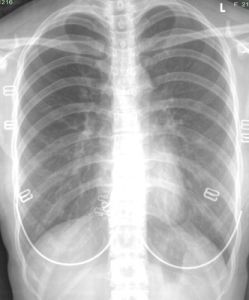

胸腔透視檢查,必要時進行CT掃描。

胸膜增厚首先是由胸膜炎所致。有的達2厘米以上,由纖維結締組織組成,呈灰白色,表面為肉芽組織,膿腔內有大量壞死組織及積膿並有分隔胸膜炎有兩種,一種為乾性胸膜炎(無胸腔積液),另一種為滲出性胸膜炎(有胸腔積液)。產生胸膜肥厚主要是由於得過第二種胸膜炎。由於胸水沒及時發現和抽水治療,胸水在胸膜腔內停留時間長了,胸水刺激胸膜加上胸水中有纖維蛋白附在胸壁上故使胸膜增生增厚。